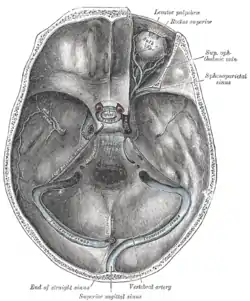

The sinuses at the base of the skull. (Visible as light blue circle at center.) | |